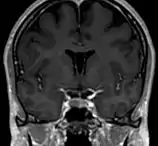

Septum pellucidum

Le septum pellucidum, est une membrane verticale, fine, triangulaire séparant les cornes antérieures des 2 ventricules latéraux du cerveau, passant du corps calleux jusqu'au fornix.

Le septum pellucidum est situé sur la ligne médiane du cerveau, entre les deux hémisphères cérébraux. Il est attaché en haut au corps calleux, l'ensemble des fibres nerveuses qui connectent les 2 hémisphères. En arrière il est en rapport avec la partie antérieure du fornix, et de part et d'autre on trouve la face médiane des deux ventricules latéraux.